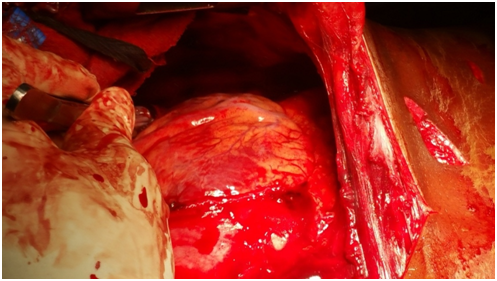

Interventions

A Size 16 cannular was inserted in the 2nd intercostals space along the midclavicular line. Air rushed out and the patients breathing was normalised. Two large bore cannulae were inserted and the Intra Vascular Fluid (IVF) was commenced. An urgent Cross-match and Full Blood Count was collected. A Chest Drain(CD) was inserted. Immediately more than 250mil of blood was drained. Because of this, the CD was clamped. The Consultant Surgeon was called out to come and attend to the patient. In the mean time the following things were done ATT O.5 mililres Intra Muscular were given .Metronidazole 500mg and Cefotaxime 1gram were Intra Venously commenced. The patient was wheeled to theatre for an urgent thoracotomy Intraoperative findings were. There was leaking out of the heart each time it contracted. This was because the ventricle left side of the heart was stabbed, it had cut about 1cm in size. A 2/0 vycril suture on the rounded needle was used (Figures 9-12).

Figure 9 The Heart being sutured.

Figure 10 The Heart sutured.